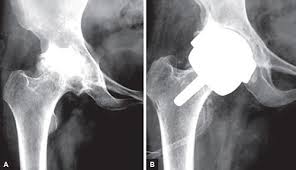

이 때에는 ‘인공관절 치환술’이 유일한 해결책으로 지목된다고 한다. 망가진 관절 대신, 그 자리에 새로운 관절을 이식하는 것이 바로 ‘인공관절 치환술’이라고 한다.

인공관절 수술은 원리에 따라 다양하게 나뉘며 닳아 없어진 무릎 연골 대신 인체에 해가 없는 코발트크롬, 티타늄합금 등의 금속이나 세라믹으로 만들어진 인공관절을 삽입하는 과정으로 진행된다고 한다. 다만 환자 입장에선 자신에게 적합한 수술법을 찾는 것이 더욱 중요해졌다고 한다.